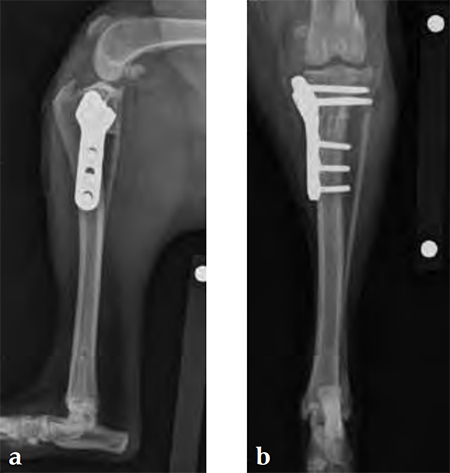

Case 2: Australian cattle dog

(Case provided by Brian Beale, Houston, USA)

An 8-year-old, female, spayed, 24 kg Australian cattle dog. This breed has short stocky legs and is very energetic and strong. The added strength of the 3.5 mm plate over the TPLO 2.7 mm plate was an advantage. The smaller head profile and shorter length of the TPLO 3.5 mm small stature plate allowed it to fit nicely on this patient.